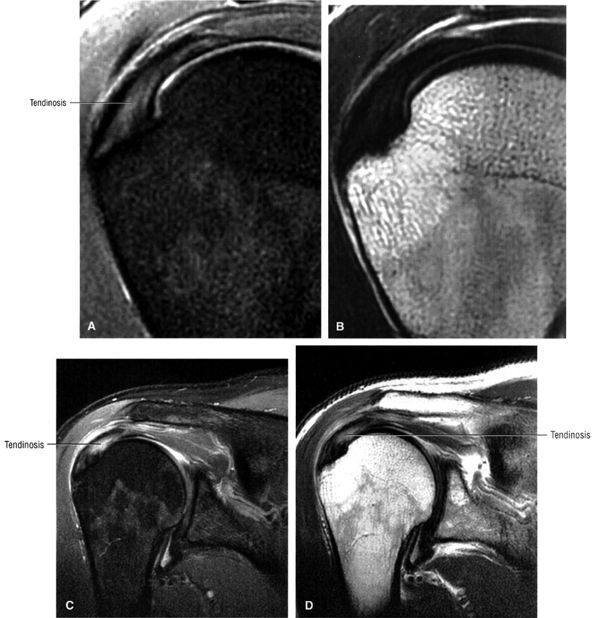

FIGURE 8.2 ● Rotator cuff tendon on coronal FS PD FSE (A) and T2 FSE (B) images using an eight-channel phased-array coil.